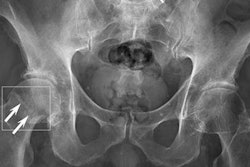

Between April 2019 to April 2020, 1.2 million patients presented to an emergency department in the U.K. with acute fractures or dislocations, an increase of 23% from the year before. Missed or delayed diagnosis of fractures on radiographs is a common diagnostic error, ranging from 3% to 10%. Thus, an increasing number of studies apply artificial intelligence (AI) techniques to fracture detection as an adjunct to clinician diagnosis, the authors wrote.

Thirty-seven studies identified fractures on radiographs, of which 18 focused on lower limb, 15 on upper limb, and four on other fractures. Five studies identified fractures on CT images.